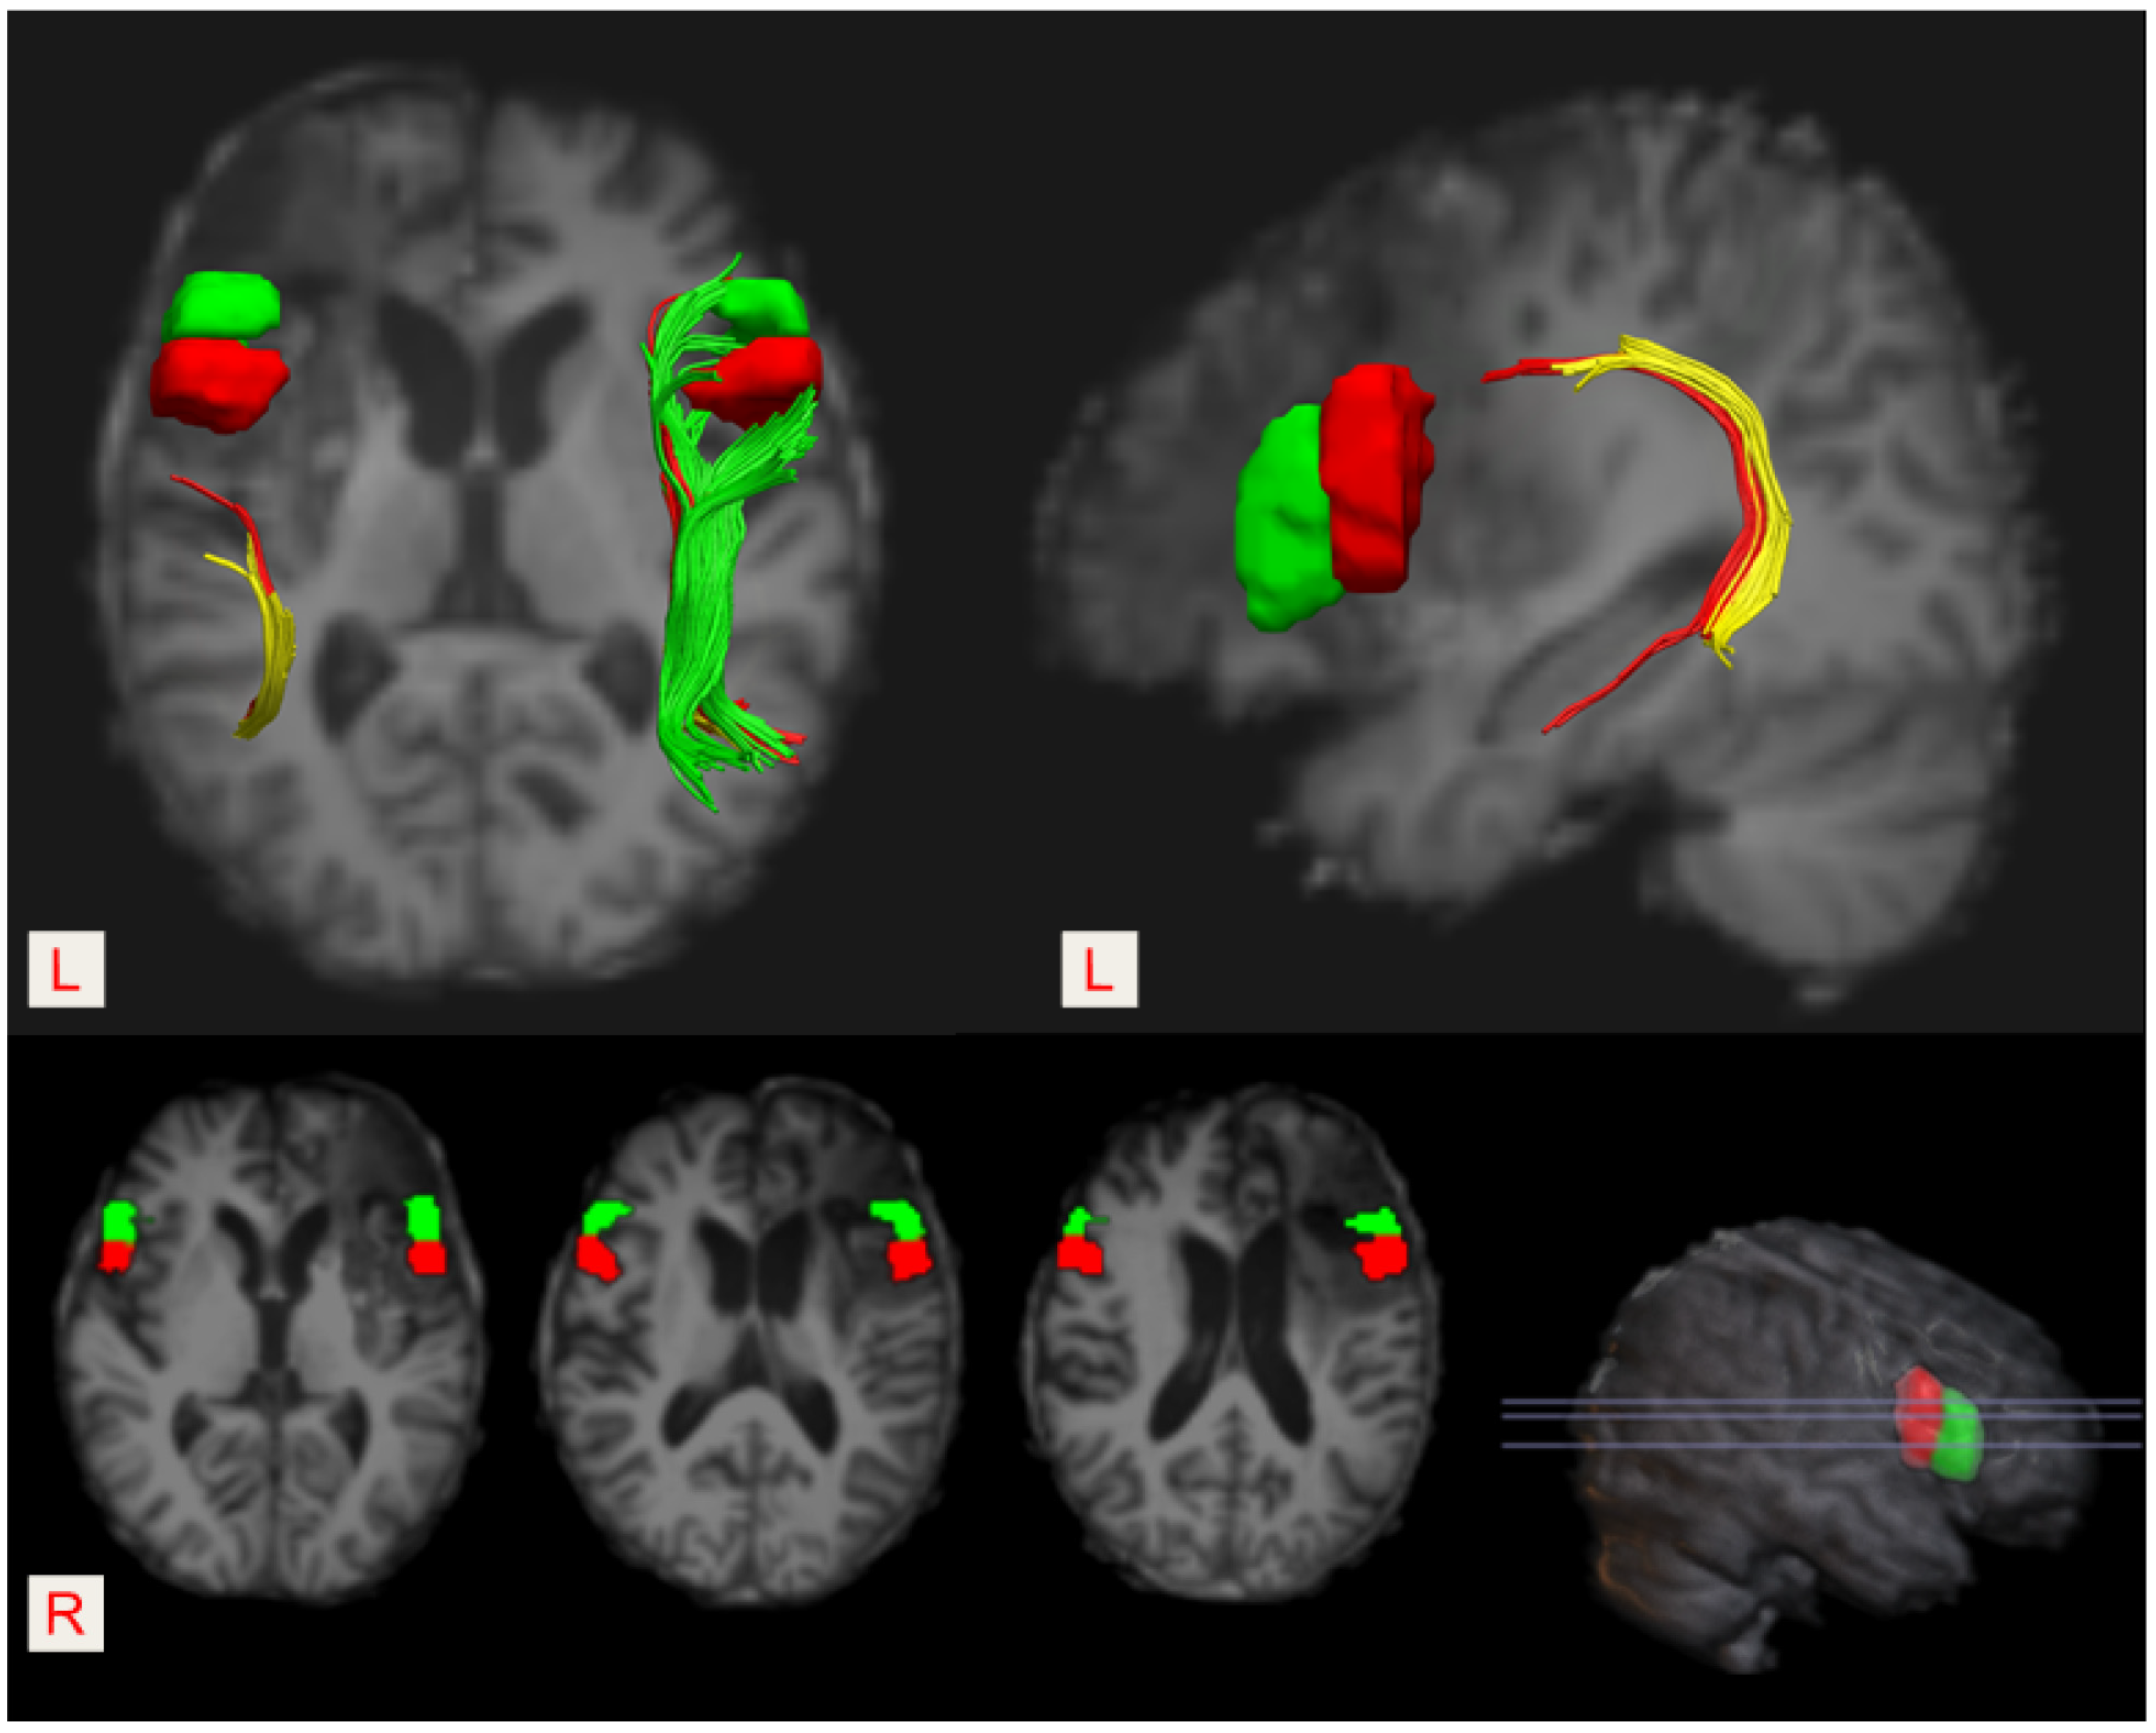

3. Diffusion Tensor Imaging and Tractography Evaluation